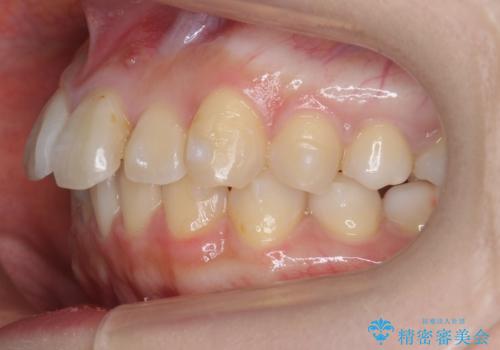

軽度の前歯のがたつき 下の前歯が生まれつき少ない

- 前歯のがたつきを主訴に来院。

下の前歯が生まれつき3本でした。

そのため、上の前歯が少し余るような形で出っ歯になっていたため、スペースを作って引っ込めています。

下を3本でそのまま並べてあるため、上下の正中は合いません。

合わせようとすると抜歯か、下の隙間を無理やり開けてブリッジとなりますが、そこまでするメリットがないため、下はそのままの歯の数を生かしています。